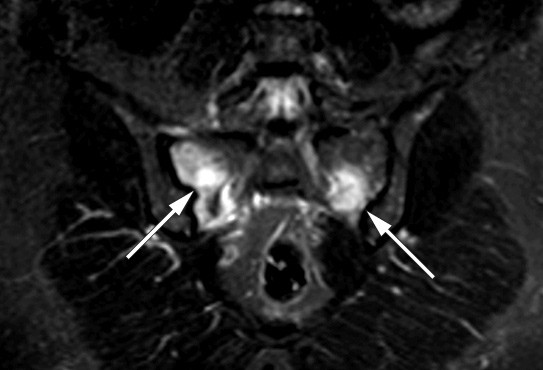

Kvinnen utviklet så gradvis økende smerter fra korsryggen ut i begge glutealregioner. Blodprøver viste normalt kalsium-, lavt fosfat- og forhøyet ALP-nivå, PTH i øvre normalområde, normale 25-OH-vitamin D og 1,25(OH)2-vitamin D-verdier. MR-undersøkelse (STIR-sekvens) viste høysignalforandringer i begge sakralvingene og etter hvert på ileumsiden, tydende på betydelig knokkelødem (bildet til venstre). Det var oppklaringslinjer i sakralvingene som kunne gi mistanke om insuffisiensfraktur bilateralt. Helkroppsscintigrafi viste økt opptak i fremre del av os frontale på begge sider av midtlinjen, i flere costae, begge ileosakralledd og proksimalt i venstre tibia.

Behandlingen består i å seponere tilskudd av jernsakkarider, eventuelt gi tilskudd av peroral fosfat og vitamin D (2). Heldigvis ser det ut til at nyretubulidysfunksjonen og osteomalasien er reversible, men alvorlige beindeformasjoner kan være permanente. Ved kontroll fem måneder etter seponering av alle jerntilskudd, var pasienten i bedring. MR viste regress av patologiske forandringer (bildet til høyre). Pasienten trenger imidlertid fremdeles behandling for jernmangelanemien og får nå en annen type intravenøst jerntilskudd. Transfusjonsbehovet varierer, avhengig av hvor ofte hun får jern.